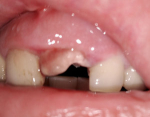

- На 2-3 день на месте удаленного зуба появляется белесая пленка.

У многих пациентов вызывает беспокойство белое пятно, которое образуется на месте удаленного зуба спустя пару дней. Переживать из-за него не стоит, ведь это абсолютно нормальное явление.

Пленка белого цвета – это образующийся из плазмы белок фибрин. Он появляется вследствие некроза клеток, которые «выходят» наружу, уступая место новому эпителию. В слюне человека есть специальное вещество, стабилизирующее фибрин.

Фибринозный белый налет выполняет важную функцию: он защищает лунку от проникновения болезнетворных микроорганизмов и механических травм. Чаще всего заметная плотная пленка появляется на ране после удаления зуба мудрости (рекомендуем прочитать: что делать, если болит десна после удаления зуба мудрости?). Пациенты принимают ее за скопления остатков пищи или гноя. Попытки вымыть фибриновое наслоение приводят к прерыванию регенеративного процесса. В рану может попасть инфекция.

Стоит помнить, что до образования белой фибриновой пленки нельзя использовать ментоловые ополаскиватели для уничтожения болезнетворных микроорганизмов, иначе кровяной сгусток может выпасть. Как выглядит налет на месте вырванного зуба, можно увидеть на фото.